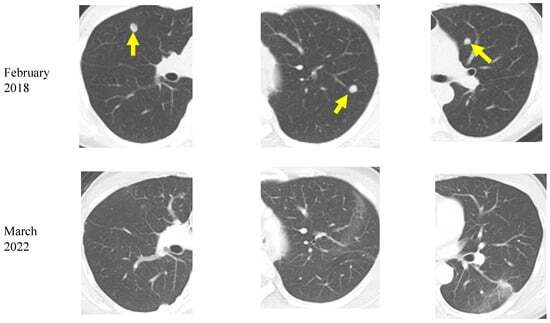

A 48-year-old woman was diagnosed with RAS-mutant colon cancer and multiple bilateral lung metastases in December 2016. After laparoscopic low anterior resection, she was treated with six cycles of Xelox (capecitabine and oxaliplatin) and two cycles of Xeloda (capecitabine) as adjuvant chemotherapy. However, a CT in February 2018 showed the appearance of new lung metastatic lesions. In April 2018, the patient was referred to our institution, and she started a ketogenic diet at age 50. She also continued standard chemotherapy at the other institution. Between January and March 2019, radiofrequency ablation (RFA) was performed at the other institution for bilateral lung metastases. Liver metastases were found in June, and transarterial embolization (TAE) and RFA were performed in July. A CT in December showed reduced lung and liver metastases. During the above treatment, the patient continued a ketogenic diet. Chest and abdominal CT in March 2022 showed no increase in liver or lung metastatic lesions (Figure 5). As of March 2023, the patient was 55 years old, continues on a ketogenic diet, and was in good general condition. During treatment, potassium chloride and statins were administered orally for mild hypokalemia and hyperlipidemia, respectively, but no serious side effects were observed.

Figure 5. Chest computed tomography images of a colorectal cancer patient with lung metastases (yellow arrows). A decrease in bilateral multiple lung metastases 4 years after the start of the ketogenic diet is seen.